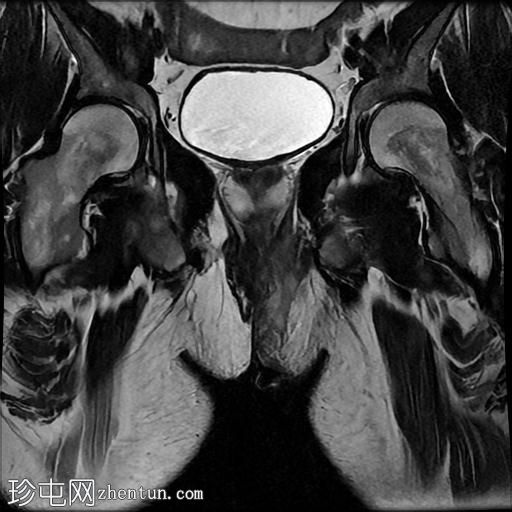

冠状位

T2

冠状位T2

脂肪饱和度

一条68毫米厚的强化通道始于左侧肛周区域,向上穿过肛门内外括约肌,在2点钟方向开口于肛管。

无脓肿形成。

MRI成像特征与所述左侧经括约肌肛周瘘相符。